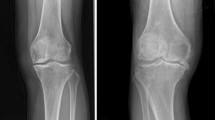

Osteoarthritis (OA) represents the most prevalent and disabling arthritis worldwide, affecting several diarthrodial joints, but primarily the knees and hips. Its worldwide incidence rate is approximately 1/10 in male and 1/5 in female over 60 years of age [1]. Our understanding concerning the etiology of OA continues to grow. Many factors, including age, obesity, gender, genetics, and joint injury, have shown to contribute to the development of OA, among which increasing age and obesity are the principal factors [2]. OA is now considered a heterogeneous chronic disease involving multiple joint tissues. It is mainly characterized by the degradation of articular cartilage, subchondral bone sclerosis, osteophyte formation, variable degrees of synovitis, and ligament degeneration, eventually leading to disability in the end state of the disease [3]. The high rates of morbidity and disability associated with OA have led to a reduced quality of life and a great economic burden on society. The economic burden of OA has been estimated to be between 1.0 and 2.5% of the gross domestic product for Western countries [4]. Despite this challenge, there are no effective early diagnostics or main therapeutics for this disease [5]. These statistics could be improved if the understanding of the diagnostic biomarkers and metabolic alterations in OA were clearer [6].